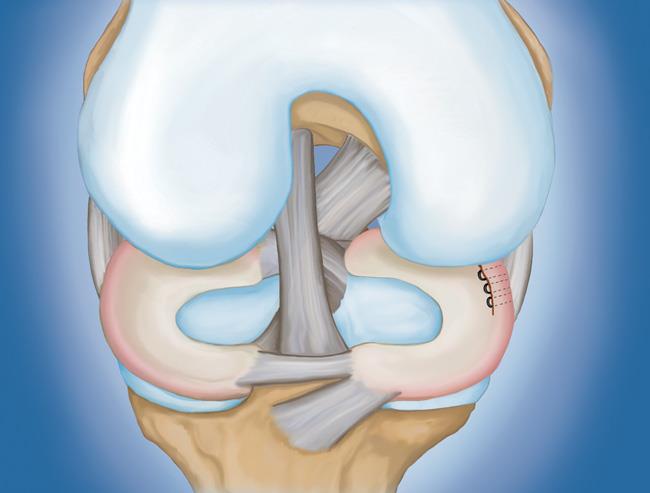

• 半月板修復(fù)。  一些半月板撕裂可以通過(guò)將撕裂的碎片縫合(縫合)在一起來(lái)修復(fù)。撕裂能否成功修復(fù)取決于撕裂的類(lèi)型,以及受傷半月板的整體狀況。因?yàn)榘朐掳灞仨氁黄鹩?,修?fù)的恢復(fù)時(shí)間比半月板切除術(shù)長(zhǎng)。

用縫線修復(fù)撕裂的半月板